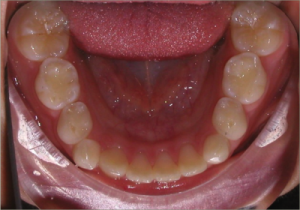

12 year old female:

Diagnosis:

- Missing upper right lateral incisor & lower right cuspid

- Horizontally impacted lower left cuspid

- Peg shaped upper left lateral incisor

Treatment:

- Extraction of impacted lower left cuspid, and peg shaped upper left lateral incisor

- Upper cuspids substituted as laterals

- Full fixed appliances

- 20 months